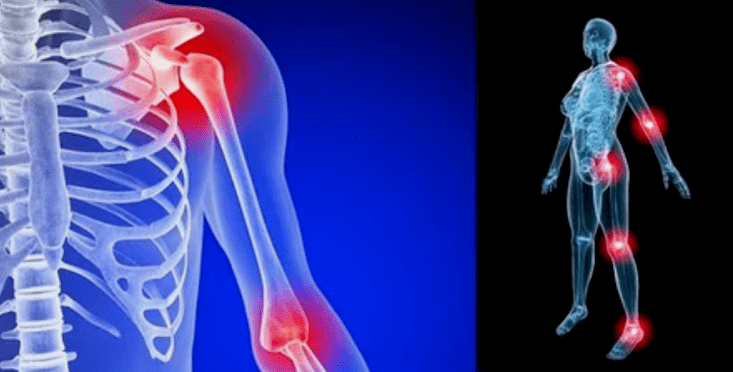

The manifestations of the disease differ little depending on the location, the signs are more frequently reflected on the knees, shoulders and hip joints, due to high load.

- pain.They have low gravity in the initial stage, with aggravation of the sensation status intensifies.Initially, the joints hurt only after waking up, after a warm light, the sensations disappear.Over time, the pain appear at night, they disturb a lot during and after walking, running, etc.In the last stage, pain syndrome pursues a person all the time;

- redness of redness.It is located near the sick joint, this indicates an inflammatory process and progression of the disease.The doctor understands that the synovial cover is affected, this causes the accumulation of fluid and increased pain;